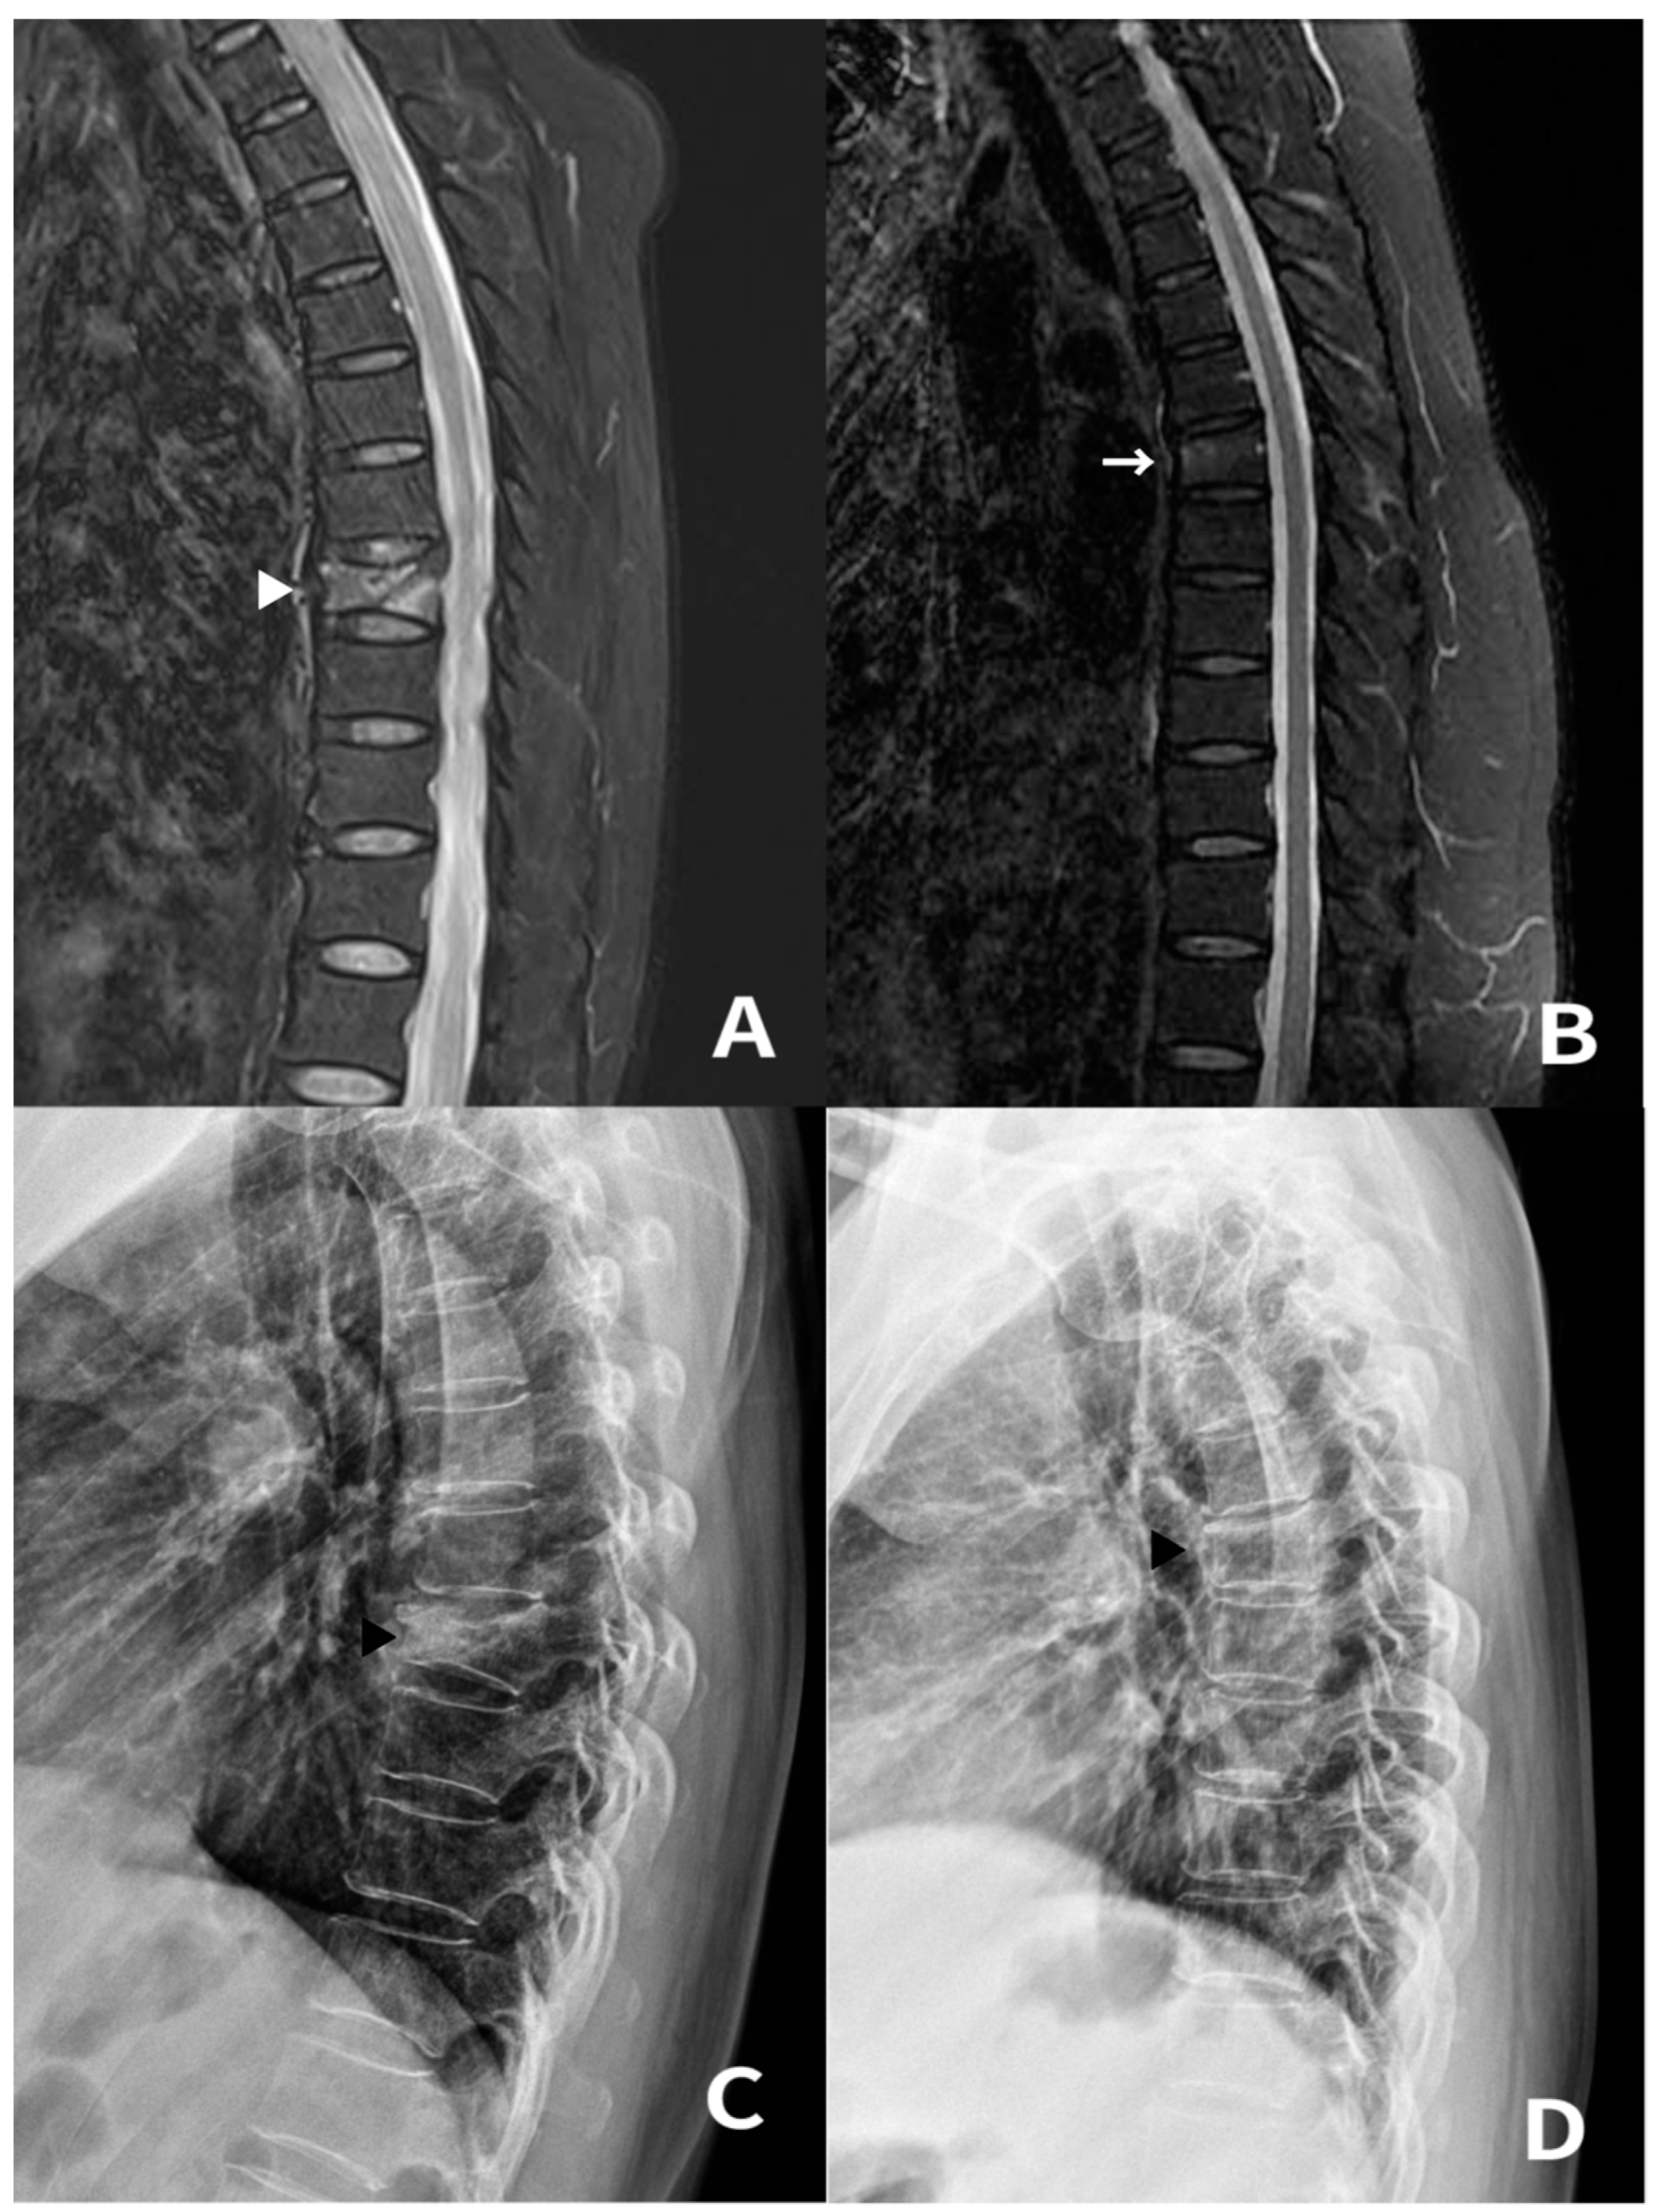

3.1. Case 1 and 2

3.2. Case 3